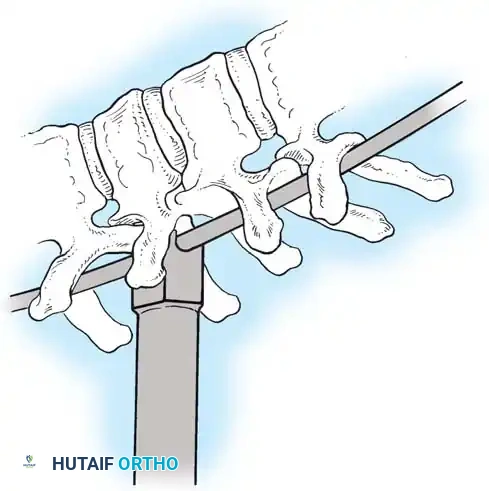

The Hall Technique

The Hall technique offers an alternative method for facet obliteration and grafting, particularly useful in rigid deformities.

Fig. 38-28: The Hall technique of facet fusion, involving sharp excision of the inferior facet and trough creation.

- Sharply amputate the inferior articular facet with a gouge and remove the bone fragment entirely. This exposes the cartilage of the superior facet.

- Remove the exposed cartilage completely with a sharp curet.

- Create a bleeding trough by removing the outer cortex of the superior facet.

- Impact cancellous bone grafts directly into this vascularized trough.

- Complete the procedure with global decortication of the posterior elements.